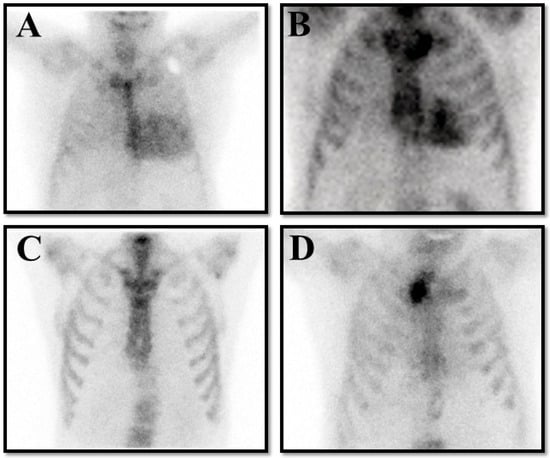

And the cardiologist should always integrate the resulting finding with clinical, electrocardiographic, and echocardiographic findings to ensure the patient’s clinical picture fits with ATTR-CM. When these precautions are taken, the specificity of a positive scan for true ATTR becomes unequivocal (Figure 3).

Figure 3. The panel represents four possible results on bone scintigraphy in patients with clinical suspicion of transthyretin cardiac amyloidosis (ATTR-CM). (A) is a true positive result compatible with Perugini grade 3. (B) is a false positive result in a patient with hypertrophic cardiomyopathy. (C) is a false negative result in a patient with hereditary ATTR-CM for a Val30Met pathological variant. (D) is a true negative result in a patient without ATTR-CM.